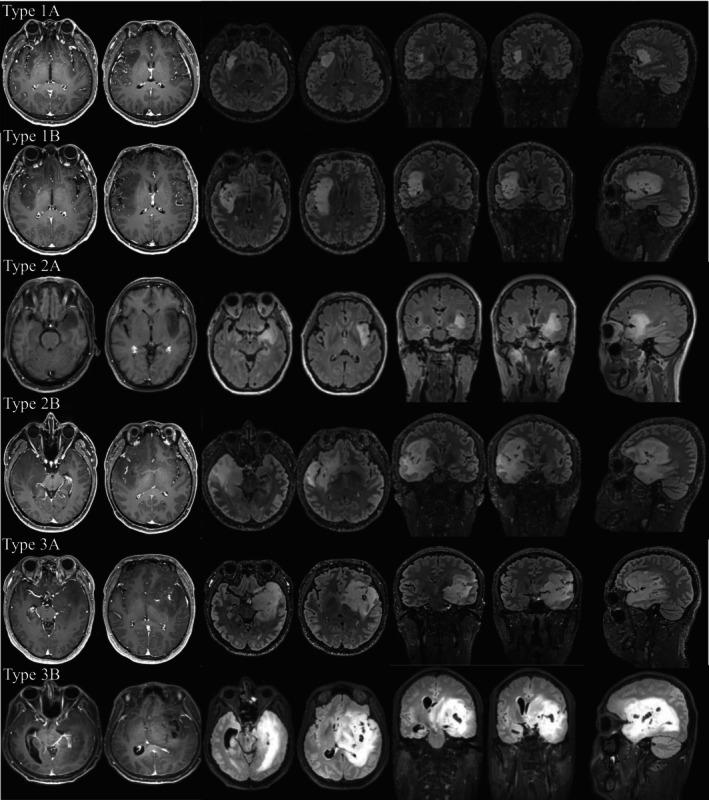

Our study included 283 consecutive patients diagnosed with histological grade 2 and 3 insular gliomas. A new classification was proposed, and tumors restricted to the paralimbic system were defined as type 1. When tumors invaded the limbic system (referred to as the hippocampus and its surrounding structures in this study) simultaneously, they were defined as type 2. Tumors with additional internal capsule involvement were defined as type 3.

方法

我们的研究纳入了 283 例组织学 2 级和 3 级岛叶胶质瘤患者。提出了一种新的分类方法,将仅限于边缘系统的肿瘤定义为 1 型。当肿瘤同时侵犯边缘系统(在本研究中指海马及其周围结构)时,定义为 2 型。肿瘤伴有额外的内囊受累,定义为 3 型。